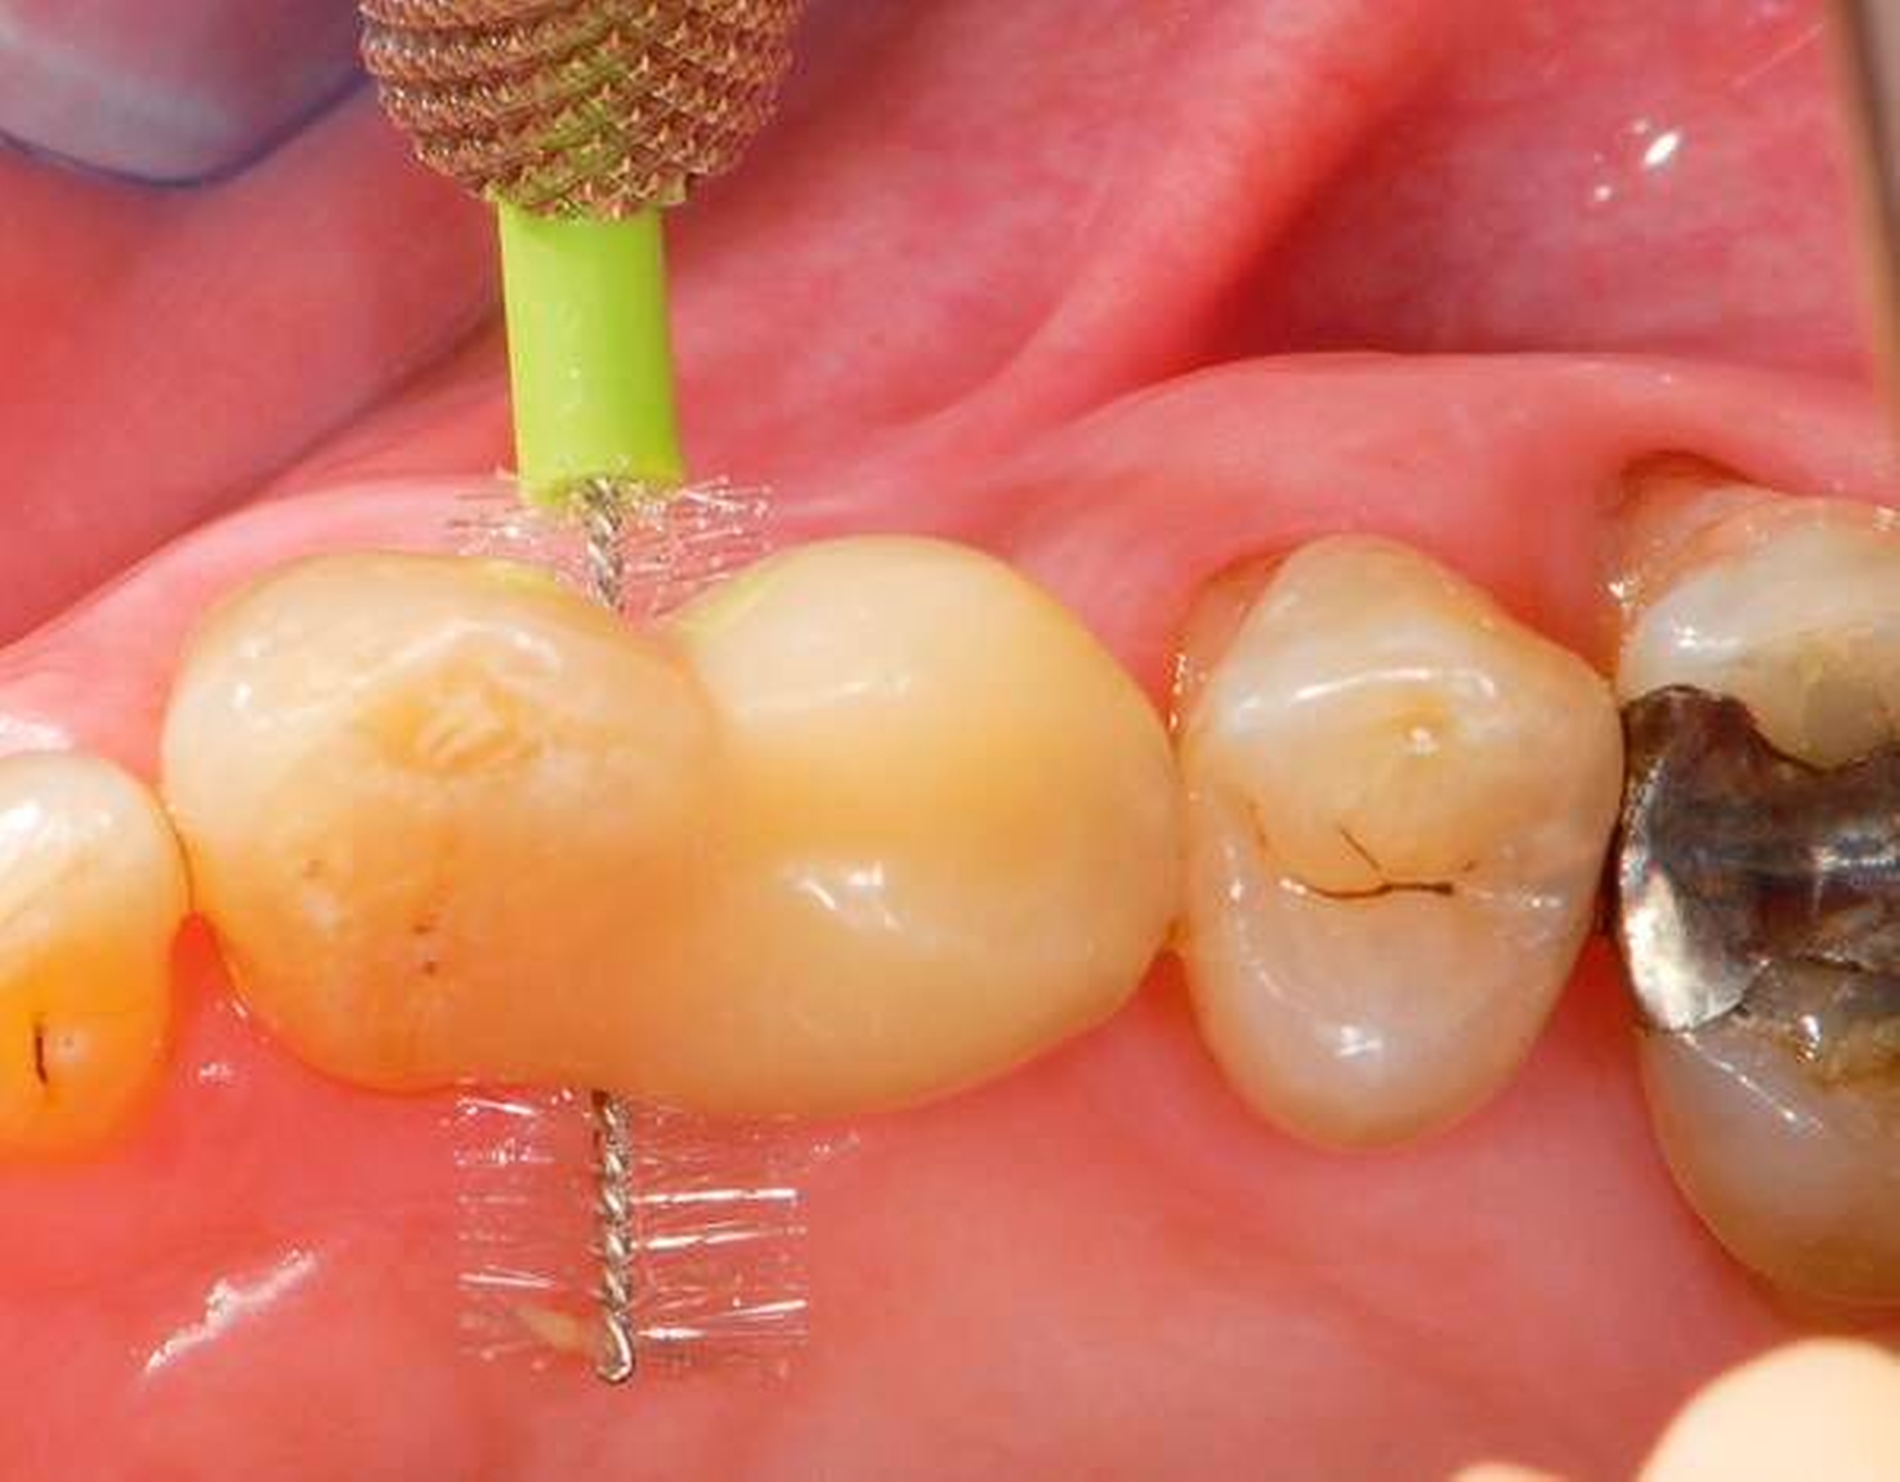

Abbildung 2: Direkte Teilüberkronung im Seitenzahnbereich (R1-Technik)

In den Abbildungen 1 bis 3 werden Optionen für frugale Interventionen auf restaurativem Sektor aufgeführt. Es handelt sich um direkte Vollüberkronungen im Frontzahnbereich (hier: hergestellt in R1-Technik / einphasig) (Abbildung 1), direkte Teilüberkronungen im Seitenzahnbereich (hier: hergestellt in R1-Technik / einphasig) (Abbildung 2), Reparatur-Restaurationen im Seitenzahnbereich (hier: hergestellt in R2-Technik / zweiphasig) (Abbildung 3). Technische Einzelheiten zur Vorgehensweise und den Ergebnissen sind an anderer Stelle beschrieben (Literatur siehe oben).

Für die in Abbildung 2 dargestellte Situation eines tief zerstörten Prämolaren gelten ähnliche Charakteristika. Es gibt in der restaurativen Zahnheilkunde viele Neuerungen, die das Behandlungsspektrum vergrößert haben. Dazu zählen unter anderem: